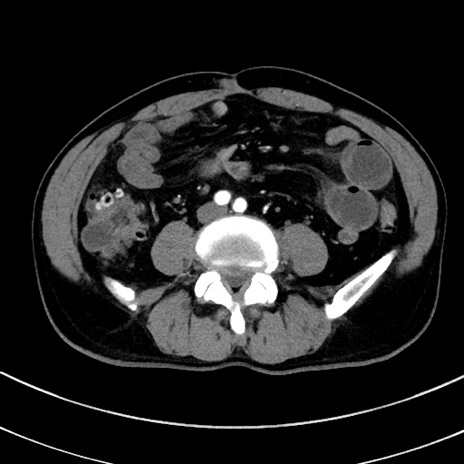

症例8(横断像)

【症例】 60歳代男性

【主訴】 黒色吐物

【現病歴】 4日前から嘔気自覚、2日前の朝食後にも嘔気あり、自分で手で嘔吐反射起こし嘔吐したところ血が混ざっていたため受診。

【既往歴】 5年前汎発性腹膜炎を伴う急性虫垂炎で手術、高血圧、前立腺肥大症、高脂血症

【身体所見】 腹部正中に手術癩痕あり 腹部平坦・軟圧痛なし膨満感あり

【データ】WBC 8400、CRP 4.54